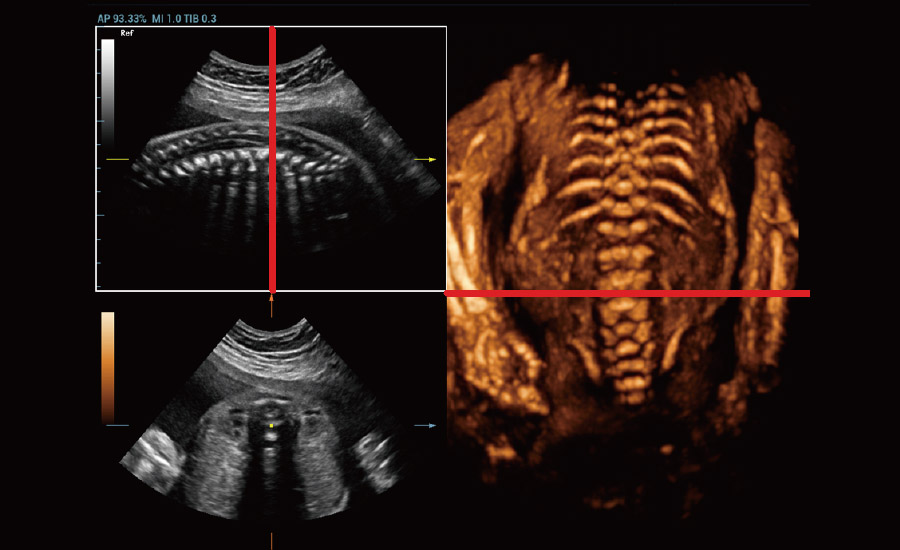

Gra?as Ć revolucionĆ”ria plataforma ZST+, o Nuewa R9 Ć© equipado com tecnologias avan?adas e inovadoras para enfrentar os desafios diagnĆ³sticos na saĆŗde da mulher. Tecnologias revolucionĆ”rias, como a angiografia ultramicroscĆ³pica (UMA), ajudam vocĆŖ a explorar mais microdetalhes e a realidade escondida. Projetado com a inestimĆ”vel sabedoria de especialistas, ele oferece informa??es completas de forma inovadora, que v?o alĆ©m de suas expectativas para diagnĆ³stico com mais confian?a, padroniza??o e eficiĆŖncia frente aos diferentes desafios em ambientes hospitalares exigentes e sobrecarregados.

A tecnologia inovadora elimina as limita??es das tradicionais imagens com Doppler. Com resolu??o espacial e sensibilidade de fluxo ultra-altas, permite a detec??o de perfus?es de fluxos muito sutis e lentos, ampliando assim a aplica??o clĆnica da avalia??o qualitativa e quantitativa do ultrassom no cĆ©rebro fetal, rins, placentas, endomĆ©trios, ovĆ”rios etc.

Por meio da combina??o de algoritmos avan?ados e do conhecimento especĆfico da regi?o, a inovadora solu??o Smart Scene permite a identifica??o automĆ”tica das caracterĆsticas do tecido e fornece diagnĆ³stico especĆfico dos Ć³rg?os com informa??es completas. Com base na identifica??o automĆ”tica de cenĆ”rios, a solu??o realiza n?o apenas a varredura 2D inteligente com configura??es e medidas automĆ”ticas, mas tambĆ©m oferece informa??es 3D abrangentes em todas as etapas, desde a otimiza??o de imagens volumĆ©tricas atĆ© a difĆcil obten??o de planos 2D, e a quantifica??o durante todo o procedimento. Ele ajuda a reduzir em grande parte a dependĆŖncia de habilidades clĆnicas, ao mesmo tempo que aumenta a precis?o, a confian?a e a eficiĆŖncia no diagnĆ³stico.